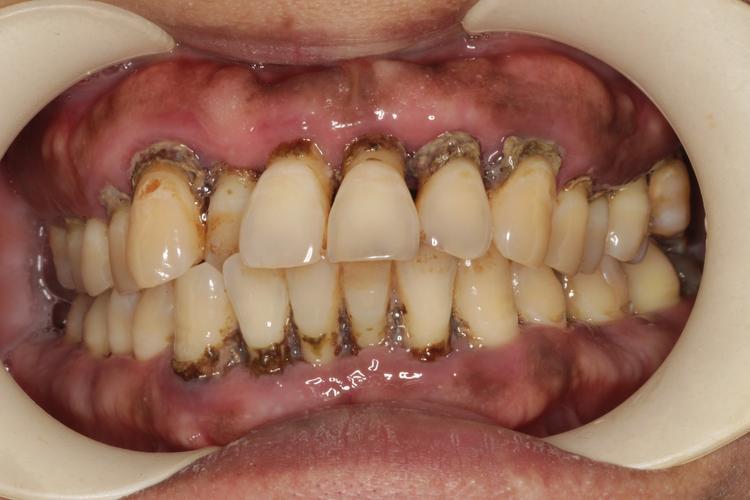

(图片来源网络,侵删)- 这是最重要的一点! 牙周炎是牙齿周围组织的炎症,如果不先彻底治疗并控制好炎症,种植牙的长期成功率会大大降低,甚至可能导致种植体周围炎、种植体松动脱落。

- 治疗流程: 需要专业的牙周科医生进行系统治疗,包括龈上洁治(洗牙)、龈下刮治、根面平整、必要时牙周手术等,直到牙周炎症得到控制、口腔卫生维护良好、牙周状况稳定(通常需要数周甚至数月)。

- 种牙前评估: 牙周稳定后,医生会评估你的牙槽骨条件(高度、宽度、密度),如果骨量不足,可能需要先进行植骨手术(GBR)或上颌窦提升等,等待骨结合(通常3-6个月)后才能种牙。